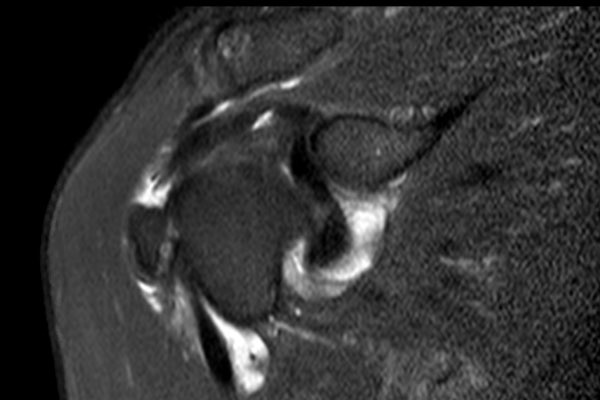

Nhấp vào hình ảnh để phóng to, sau đó cuộn qua các lát cắt.

Có hình ảnh rách toàn bộ chiều dày gân cơ trên gai kèm co rút và teo cơ.

Lưu ý các dải mỡ trong cơ tròn bé, cơ trên gai và cơ dưới gai.